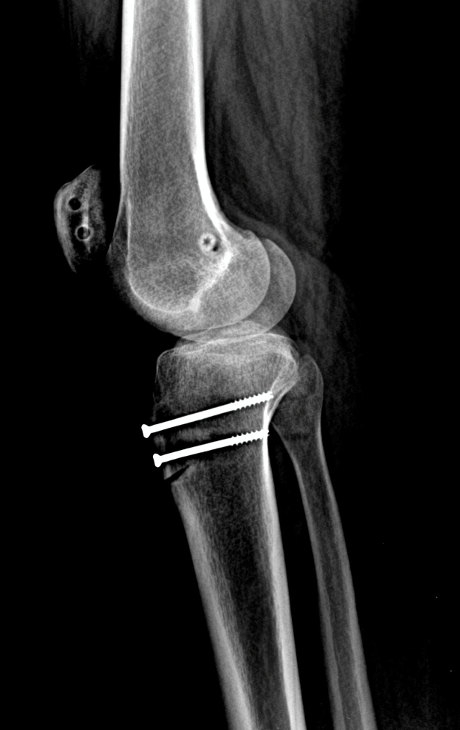

Example X-ray Images

MPFL Reconstruction with Tibial Tubercle Osteotomy